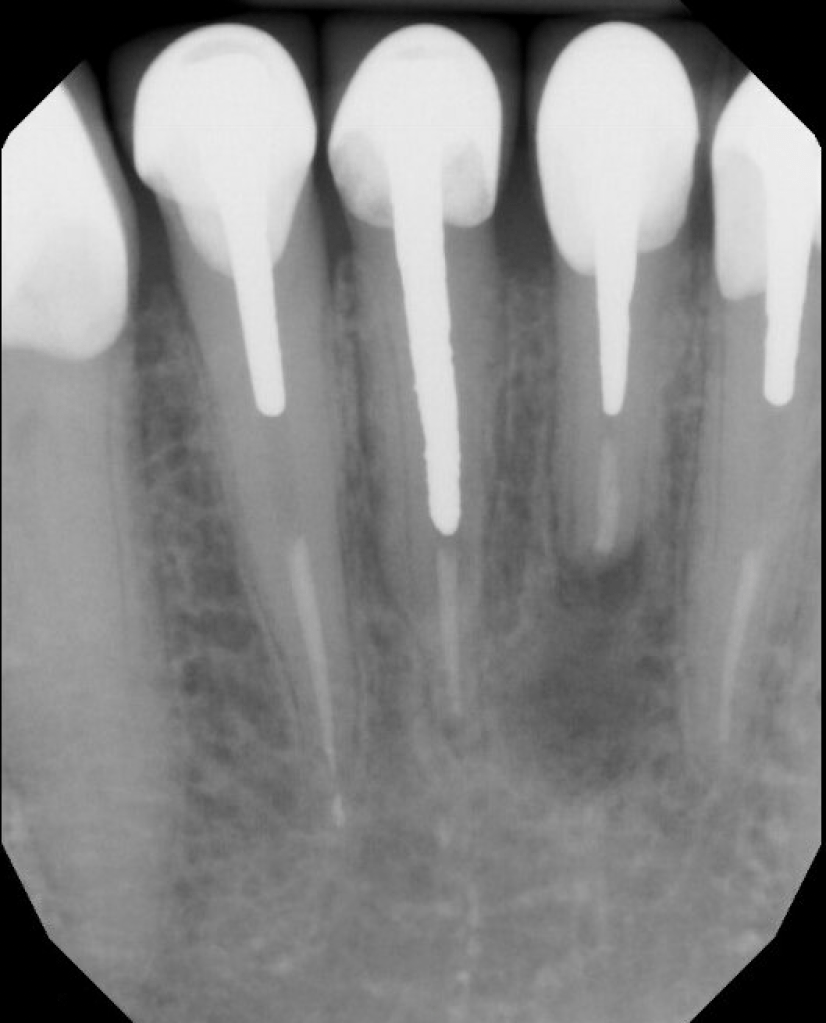

#30 NS-ReTx

Dx: Previously Treated with SAP